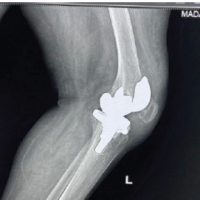

Imaging

Standing radiographs showed no abnormalities. Magnetic resonance imaging (MRI) demonstrated a well-encapsulated lobulated mass (30 × 10 × 27 mm) with fat-signal intensity in all sequences, located between the medial patellar facet and medial retinaculum, compressing Hoffa’s fat pad (Fig. 1). The cruciate ligaments and menisci were intact.

Figure 1: Sagittal magnetic resonance imaging (T1-weighted) images showing a hyperintense intra-articular mass in the inferomedial recess.